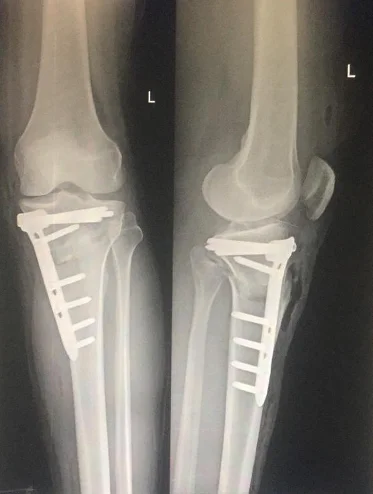

Medial Opening Wedge

In the medial opening wedge technique, a controlled gap is created on the inner side of the tibia. The opened space is stabilized with a plate and screws and is supported with bone graft if necessary.

• The surgeon makes a controlled cut in the upper shin bone (tibia)

• The bone is realigned to correct leg shape

• small plate and screws are used to hold the bone in the new position